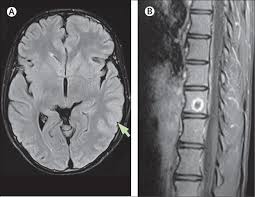

Serology for hsv showed positive hsv (1+2) igg and negative igm. Herpes simplex encephalitis occurs as 2 distinct entities: Mri in vzv encephalitis shows ischemic and hemorrhagic infarctions and demyelinating lesions. Contrast enhancement is uncommon during the first week of the disease. Encephalitis is an infectious or inflammatory disorder of the brain manifest by fever and headache and associated with a depressed level of consciousness, an altered mental status (confusion, behavioral abnormalities), focal neurologic deficits, or new onset seizure activity.

Serology for hsv showed positive hsv (1+2) igg and negative igm. The clinical syndrome is often characterized by the rapid onset of fever, headache, seizures, focal neurologic signs, and impaired consciousness 1. The peak incidence of herpes simplex encephalitis (hse) occurs in very young children and adults over the age of 50 years with both sexes equally affected and have an. Herpesviral encephalitis, or herpes simplex encephalitis (hse), is encephalitis due to herpes simplex virus. There is no particular age, sex, or seasonal predilection. Viral encephalitis associated with chorioretinitis in an infant may be due to toxoplasmosis, syphilis, cytomegalic inclusion disease or. It is estimated to affect at least 1 in 500,000 individuals per year, and some studies suggest an incidence rate of 5.9 cases per 100,000 live births. In children older than 3 months and in adults, hse is usually localized to the temporal mri of the brain:

It is estimated to affect at least 1 in 500,000 individuals per year, and some studies suggest an incidence rate of 5.9 cases per 100,000 live births. Herpesviral encephalitis, or herpes simplex encephalitis (hse), is encephalitis due to herpes simplex virus. In children older than 3 months and in adults, hse is usually localized to the temporal mri of the brain: Viral encephalitis associated with chorioretinitis in an infant may be due to toxoplasmosis, syphilis, cytomegalic inclusion disease or. This is the first study that compared the serum sodium levels. Serology for hsv showed positive hsv (1+2) igg and negative igm. There is no particular age, sex, or seasonal predilection. Imaging in acute herpes simplex.